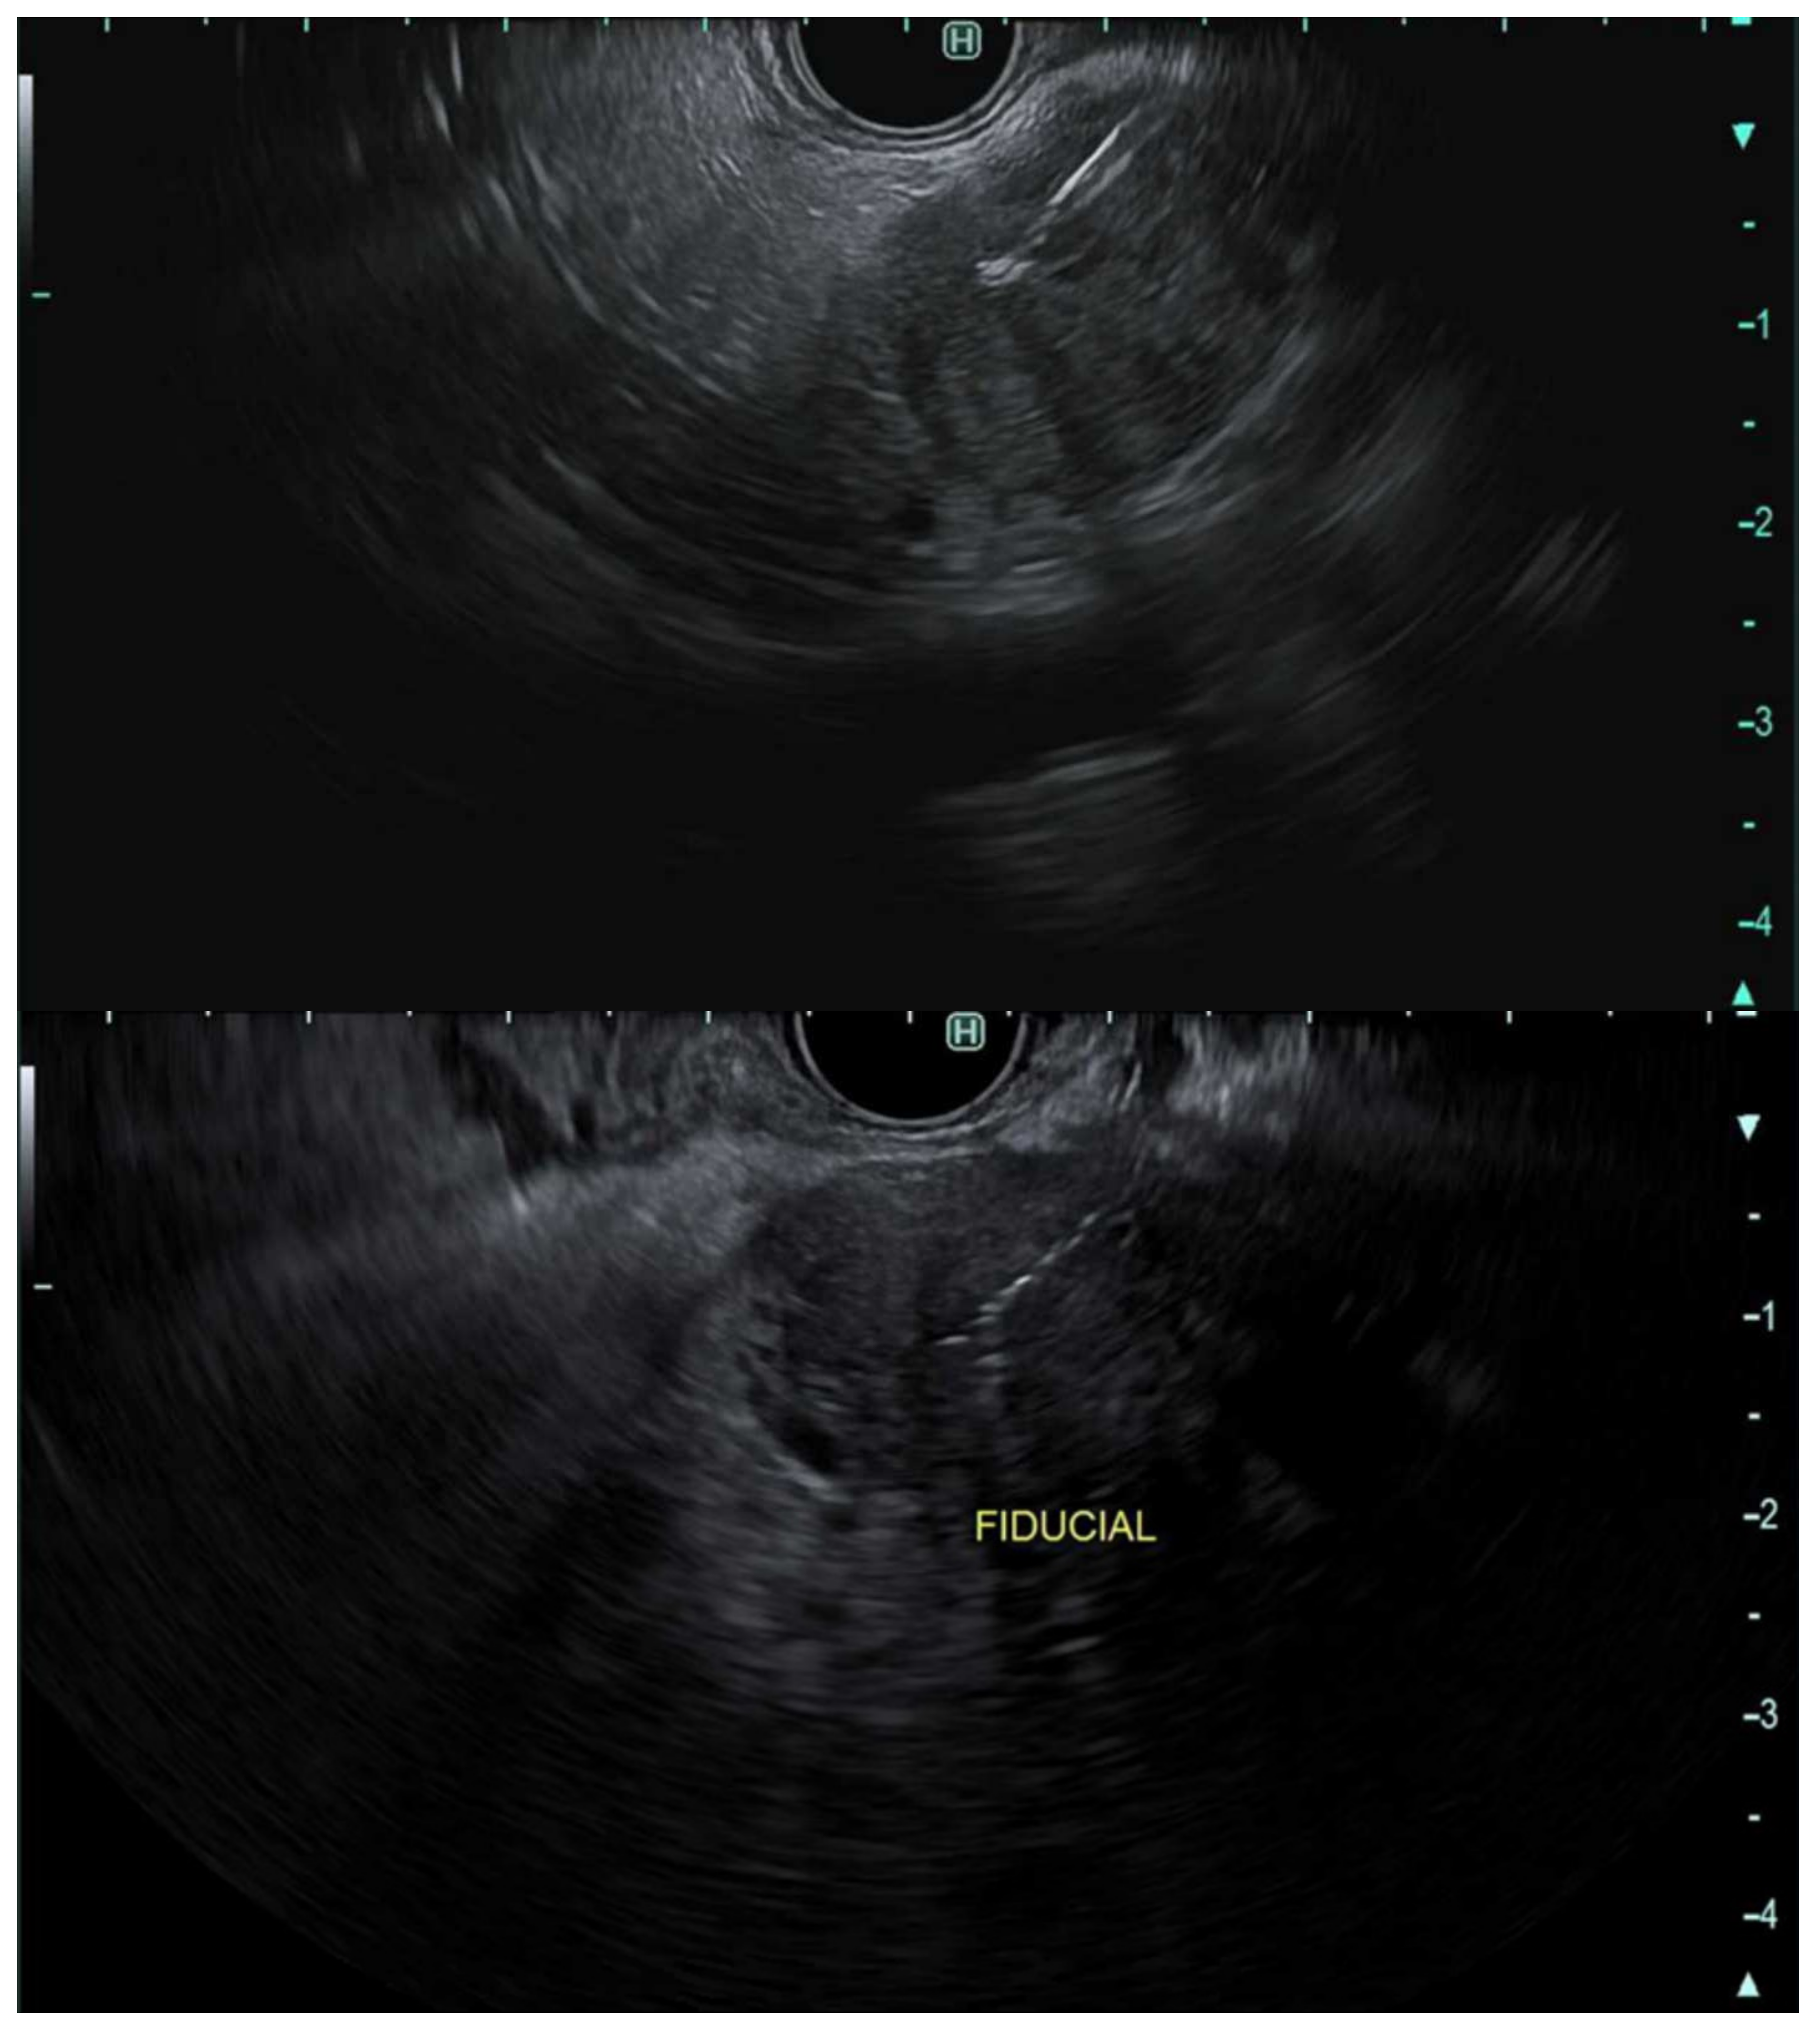

- Dhadham, G.C.; Hoffe, S.; Harris, C.L.; Klapman, J.B. Endoscopic ultrasound-guided fiducial marker placement for image-guided radiation therapy without fluoroscopy: Safety and technical feasibility. Endosc. Int. Open 2016, 4, E378–E382. [Google Scholar] [CrossRef]

- Coronel, E.; Singh, B.S.; Cazacu, I.M.; Moningi, S.; Romero, L.; Taniguchi, C.; Herman, J.M.; Bhutani, M.S. EUS-guided placement of fiducial markers for the treatment of pancreatic cancer. VideoGIE 2019, 4, 403–406. [Google Scholar] [CrossRef]